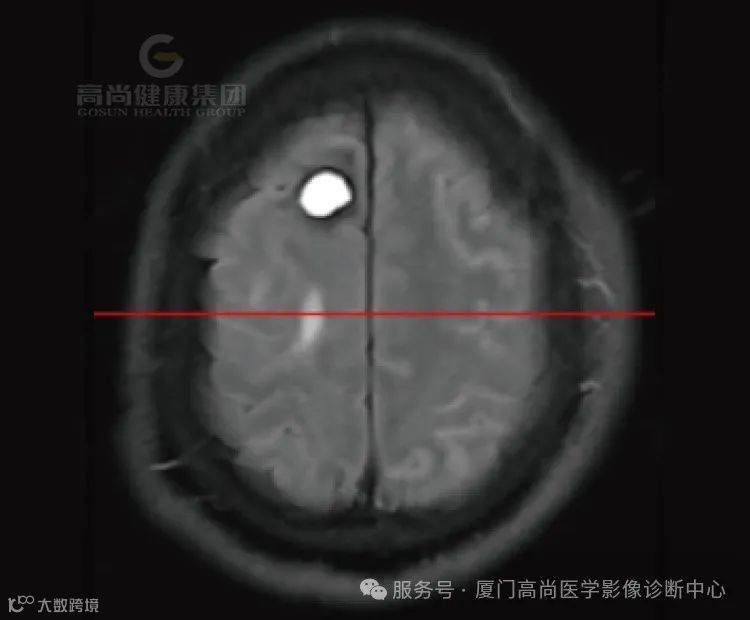

1.右侧丘脑、基底节、放射冠区病灶,考虑脑出血(亚急性期)并破入右侧脑室,中线结构局部左偏,请结合临床。

3.脑白质病变(Fazekas评分,3分)。

(1)亚急性早期(3-6d):血肿中心在T1呈等信号,外周呈高信号,且高信号逐渐向中心扩展;在质子加权和T2呈低信号。

(2)亚急性晚期(1-4周):T1和T2上均呈高信号,灶周水肿,占位效应逐渐减轻。